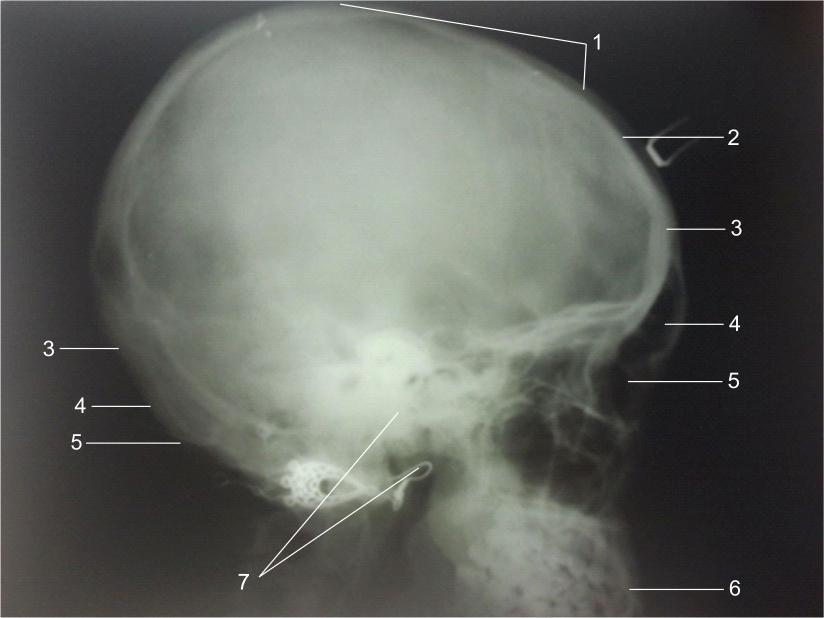

Анатомия детского черепа: Рентгеновские снимки и описание